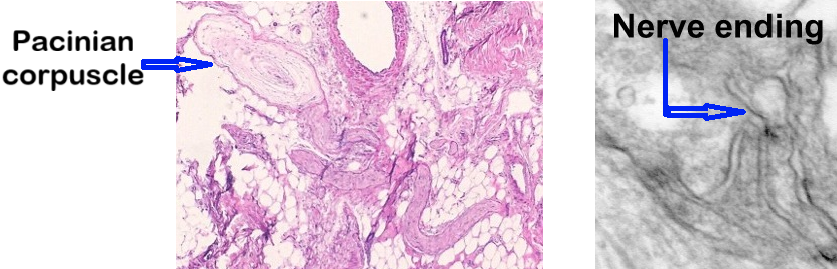

Microphotographs on Fig. 1 illustrates the comparative anatomy of a Pacinian corpuscle (a receptor specialized for vibration detection) and a NC – free ending . As the image shows, the Pacinian corpuscle has a clearly visible capsule around it, while the NC appears simply as branching nerve endings with no enclosure.